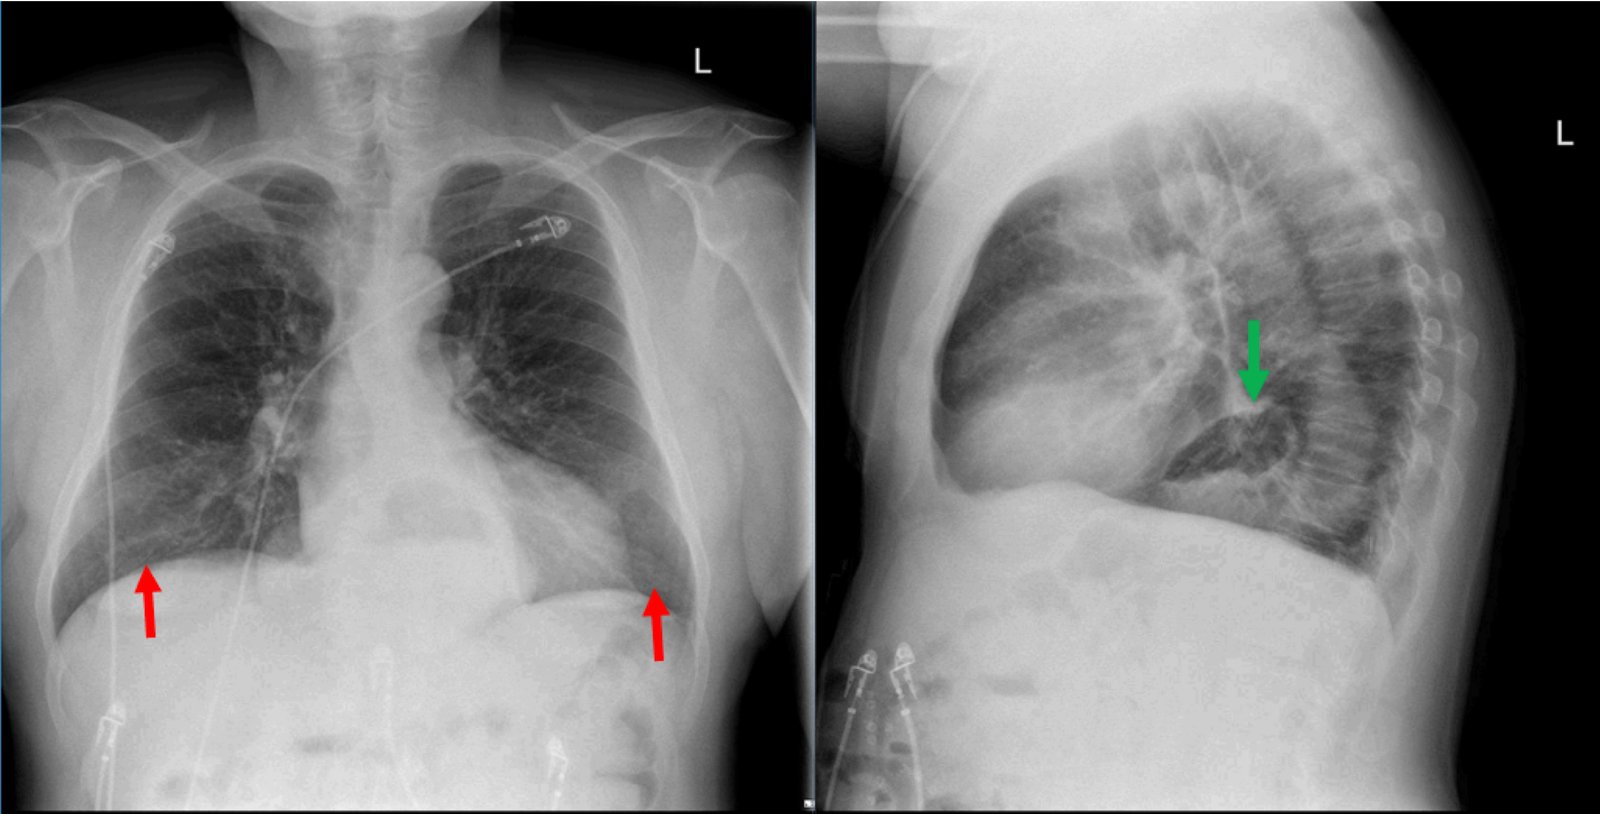

The two-view chest X-ray shows mild opacification of the bilateral lower lobes concerning for pneumonia (red arrows). Incidental retrocardiac opacity with air-fluid level consistent with large hiatal hernia is also observed (green arrow).

Patients with HHs can be asymptomatic or have symptoms such as epigastric fullness, postprandial distress, regurgitation, nausea, chest pain, or cough.4,5 Radiography studies, especially an upper GI barium series, are the preferred examination method to diagnosing HHs with a sensitivity of 77%.6 The primary diagnostic finding is a retrocardiac air-fluid level located within a paraesophageal hernia or intrathoracic stomach.1 Asymptomatic hernias may not require treatment. HH with reflux disease can be managed medically. Symptomatic HHs and paraesophageal hernias might require surgical intervention; thus surgical consultation is recommended.4

In this case, the chest X-ray was concerning for pneumonia, and a large, incidental hiatal hernia was also appreciated. Patient was started on antibiotics for the pneumonia and admitted to internal medicine. The hiatal hernia was not operated on because the patient was asymptomatic.